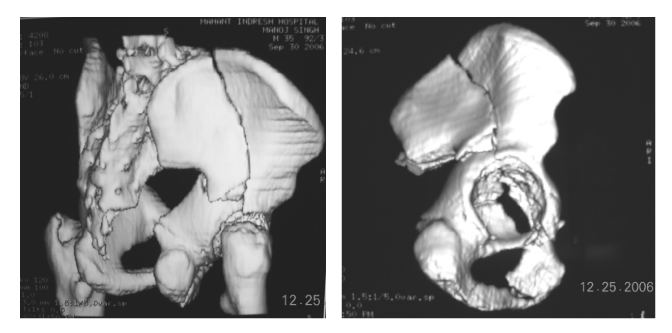

On the basis of the classification and the specific configuration of the fracture judged on radiographs and 3D CT scans a single operative approach was selected if the entire reduction could be performed with use of one approach (Figure 2A & 2B). The Kocher-Langenbeck approach was used in 12 hips (43 per cent); the ilioinguinal approach was used in 12 hips (43 per cent); and the extended iliofemoral approach was used in one (4 per cent). In three hips (11 per cent), an initial Kocher-Langenbeck or ilioinguinal approach was inadequate to complete the reduction and fixation and a combined ilioinguinal and Kocher-Langenbeck approach was used, during the same session of anesthesia. The extended iliofemoral approach was used for associated anterior wall and anterior column fractures. The Kocher-Langenbeck approach was used for posterior wall, posterior column, and posterior column-posterior wall fractures. The ilioinguinal approach4 was used for anterior column, and both column fractures with greater displacement of anterior column. The reduction was performed by direct manipulation of the bone with special reduction instruments with the goal to achieve an anatomical reduction of the acetabulum. The posterior stable fragment attached to the sacroiliac joint was used as the starting point and all fractures were reduced from posterior to anterior. The fixation was performed with plates and screws in 27 hips (96 per cent) and with screws alone in 1 hip (4 per cent) with a posterior wall fracture.2 Fixation with interfragmentary screws, with the reduction held with reduction forceps or clamps, was usually performed before fixation with a plate. Kirschner wire fixation was used for very small fragments to augment fixation achieved by a screw. Duration of Surgery ranged from 2 1/2 hours to 5 hours. The duration of the operation varied according to the operative approach. Combined approaches were the most time consuming. The duration of the operation decreased with increasing familiarity with the surgical approaches.

Figure 2 A, B: Dimensional CT scan of the same patient as in Figure 1 showing displaced fracture anterior column acetabulum with posterior hemi transverse fracture.